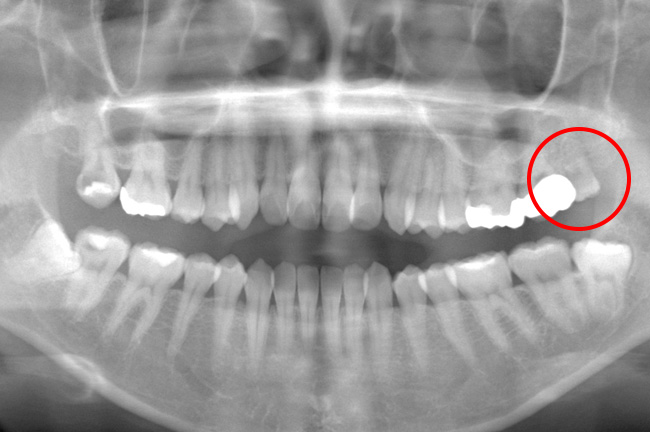

CASE 10

親知らずの根が太く曲がっていたため歯ぐきを切開し歯を分割して抜歯、2針縫合。痛みも出血もほとんどありませんでした。

治療前パノラマ

治療後CT

抜歯後

基本情報

| 年齢・性別 | 50代・女性 |

|---|---|

| 主訴 | 左下親知らず欠けた・左下8 |

| 治療内容 | 左下親知らず抜歯 |

| 治療期間 | 1回約30分 |

| 治療費 | 8,000円(2022年5月現在) |

| リスク・副作用 | 2〜3日は腫れと痛みがある。 |

| 治療方針 | 事前にCT撮影を行い歯の状態・神経との位置関係を確認して抜歯をした。 |